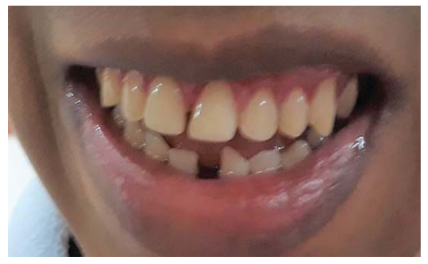

Paciente masculino de 27 años, procedente del distrito de Comas, Lima-Perú. Acude en compañía de sus padres al servicio de Estomatología de Pacientes Especiales (EPE) de la Clínica Estomatológica Central de la Universidad Peruana Cayetano Heredia. Indican como motivo de consulta dental la presencia de lesiones cariosas, dolor a la masticación y disminución de la ingesta de alimentos; con un tiempo de evolución de 15 días aproximadamente. Presenta como antecedentes patológicos: EP de inicio generalizado tipo tónico-clónico, diagnosticado a los 3 meses de edad, actualmente en controles por neurología. Indica última crisis en el 2012 y medicación actual: Carbamazepina 200 mg 1 tableta cada 12 horas. También el informante refiere el diagnóstico de DI (grado moderado).

El examen intraoral es limitado por la poca colaboración del paciente, permitiendo observar únicamente la zona anterior de ambos maxilares, en los que se evidencia acúmulos de placa dura y blanda, encías eritematosas y lesiones cariosas. Se presume presencia de lesiones cariosas en sectores posteriores, acúmulo de placa generalizada, presencia de terceros molares; como diagnósticos por confirmar.

Bajo los efectos de la AG y entubado por vía nasal, se procede a realizar la evaluación clínica, la toma de radiografías periapicales necesarias (figura 2), set fotográfico de control (figura 3), la confirmación de los diagnósticos y reconfirmación del plan de tratamiento. El plan de tratamiento incluyó: la eliminación del tártaro dental y pulido de las piezas dentarias, obturaciones de resinas y la eliminación de las terceras molares de los cuatro cuadrantes. Se consideró la permanencia de la pieza supernumeraria ubicada entre las piezas 2.2 y 2.3, por encontrarse en el arco dental sin alterar la oclusión. Se instala el tapón faríngeo, continuando así con el inicio el tiempo operatorio de 2 horas y 30 minutos. Durante la AG el paciente no presento alteraciones en su frecuencia cardiaca ni respiratoria u algún reporte de interés por parte del personal de anestesiología.